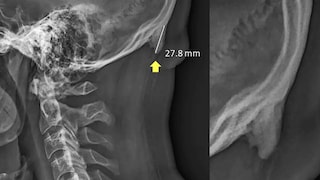

Human body transformation due to technology. A research as found that speaking on phone for long hours with tilted head forces the body to adapt. A study  in biomechanics suggests that young people are developing hornlike spikes at the back of their skulls - bone spurs caused by the forward tilt of the head. This directly is a result of a 30 degree or more tilt of the human head. The weight transfer that causes the buildup can be compared to the way the skin thickens into a callus as a response to pressure or abrasion.                 - Tathagat Banerjee